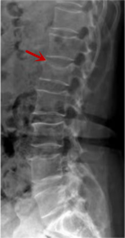

利器一:X線/DR

腰椎X線片作為最基礎(chǔ)的影像檢查手段,利于X線穿透人體組織后成像,以其快捷、直觀、價(jià)格低廉的特點(diǎn),X線檢查主要包括腰椎正側(cè)位、雙斜位以及過(guò)伸過(guò)屈位。主要用于觀察腰椎骨骼的情況,如椎體是否有骨折、骨質(zhì)增生程度、生理曲度的變化、椎體移位的情況等。然而,X線檢查也有它的局限性,無(wú)法判斷是骨折的新舊,對(duì)于椎體內(nèi)部結(jié)構(gòu)和周圍肌肉韌帶組織(如脊髓神經(jīng)、椎間盤、韌帶等)的顯示不佳,另外X線作為有輻射檢查,孕婦及嬰幼兒謹(jǐn)慎選擇。

箭頭提示腰1椎骨折

箭頭提示腰3椎體滑脫